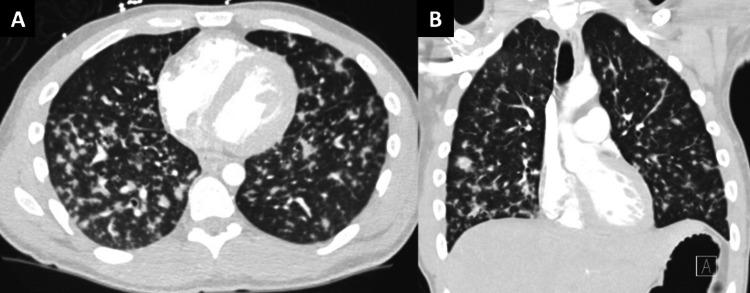

Kaposi sarcoma (KS), caused by human herpesvirus-8 (HHV-8), is among the most common malignancies in people living with HIV. Kaposi sarcoma is an angiogenic endothelial cell neoplasm and an acquired immunodeficiency syndrome (AIDS)-defining illness. Kaposi sarcoma is associated with high mortality when presenting as visceral or disseminated disease or when complicated by Kaposi sarcoma inflammatory cytokine syndrome (KICS), immune reconstitution inflammatory syndrome, or multicentric Castleman disease. We present the case of a 26-year-old male patient found to have AIDS-related KS complicated by cardiac, pulmonary, gastrointestinal, and skin involvement as well as KICS. Notably, the patient's skin lesions were not identified at the initial hospital presentation. He was treated with doxorubicin for KS and rituximab for KICS but died shortly after KICS diagnosis. We highlight the importance of recognizing KS skin lesions to aid in early diagnosis and of recognizing signs and symptoms of KICS to expedite immunomodulatory therapy initiation.

由人类疱疹病毒8型(HHV - 8)引起的卡波西肉瘤(KS)是艾滋病患者中最常见的恶性肿瘤之一。卡波西肉瘤是一种血管生成性内皮细胞瘤,也是一种获得性免疫缺陷综合征(AIDS)定义疾病。当卡波西肉瘤表现为内脏或播散性疾病,或并发卡波西肉瘤炎性细胞因子综合征(KICS)、免疫重建炎性综合征或多中心Castleman病时,其死亡率较高。我们报告一例26岁男性患者,发现患有与艾滋病相关的卡波西肉瘤,并发心脏、肺部、胃肠道和皮肤受累以及KICS。值得注意的是,患者在初次就诊时未发现皮肤病变。他接受了多柔比星治疗卡波西肉瘤,利妥昔单抗治疗KICS,但在KICS诊断后不久死亡。我们强调识别卡波西肉瘤皮肤病变以辅助早期诊断以及识别KICS的体征和症状以加快免疫调节治疗启动的重要性。